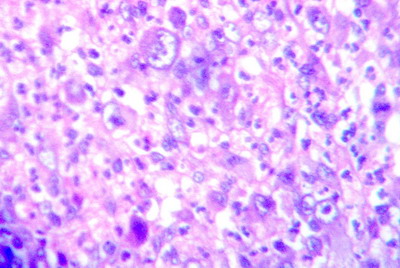

A 4 mm punch biopsy specimen was obtained from the centre of one nodule. Another excision biopsy was taken from the axillary lymph node. H & E stained sections revealed, cutaneous infiltration extended from the middle to lower dermis as well as in the subcutaneous fat. The infiltrate consisted of normal and atypical histiocytes with lymphocyte and plasma cells. The atypical histiocytes display large pleomorphic vesicular nuclei. Some of histiocytes contained in their cytoplasm phagocytes, erythrocytes, nuclear debris and fragment of leucocytes. Few cells showed typical Reed-Sternberg cells which are large histiocytic cell with several nuclei or bilobed nucleus that had a mirror image appearance (Fig.2). Lymph node biopsy showed similar findings (Fig.3).

Fig 2: Skin biopsy showed diffuse infiltration by large lymphohistiocytic cells. Some of cells showed lymphophagocytosis [H&E X 12].